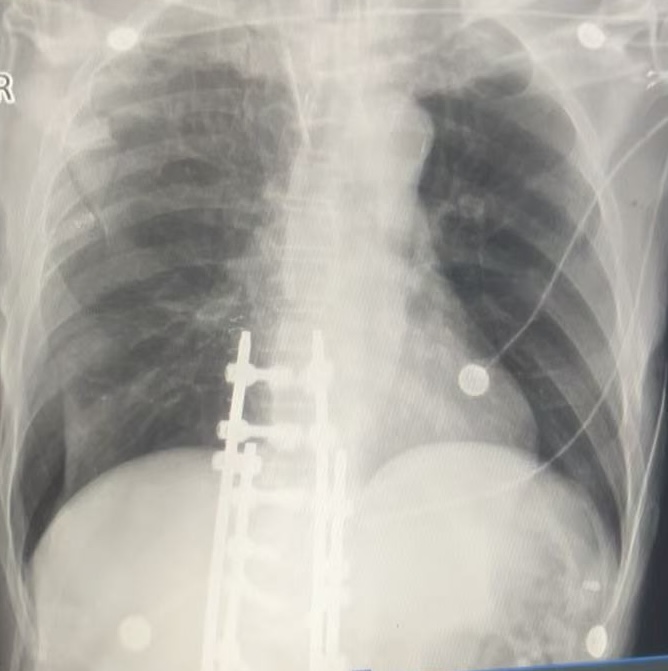

患者男性,常规骨科骨折术后入ICU监护,氧合指数大于300,常规术后床旁胸片检查。

右下肺透亮度增加,是否有气胸?查体右下肺呼吸音基本和左侧一致,超声有胸膜滑动征;

因此继续观察并早上复查胸片。